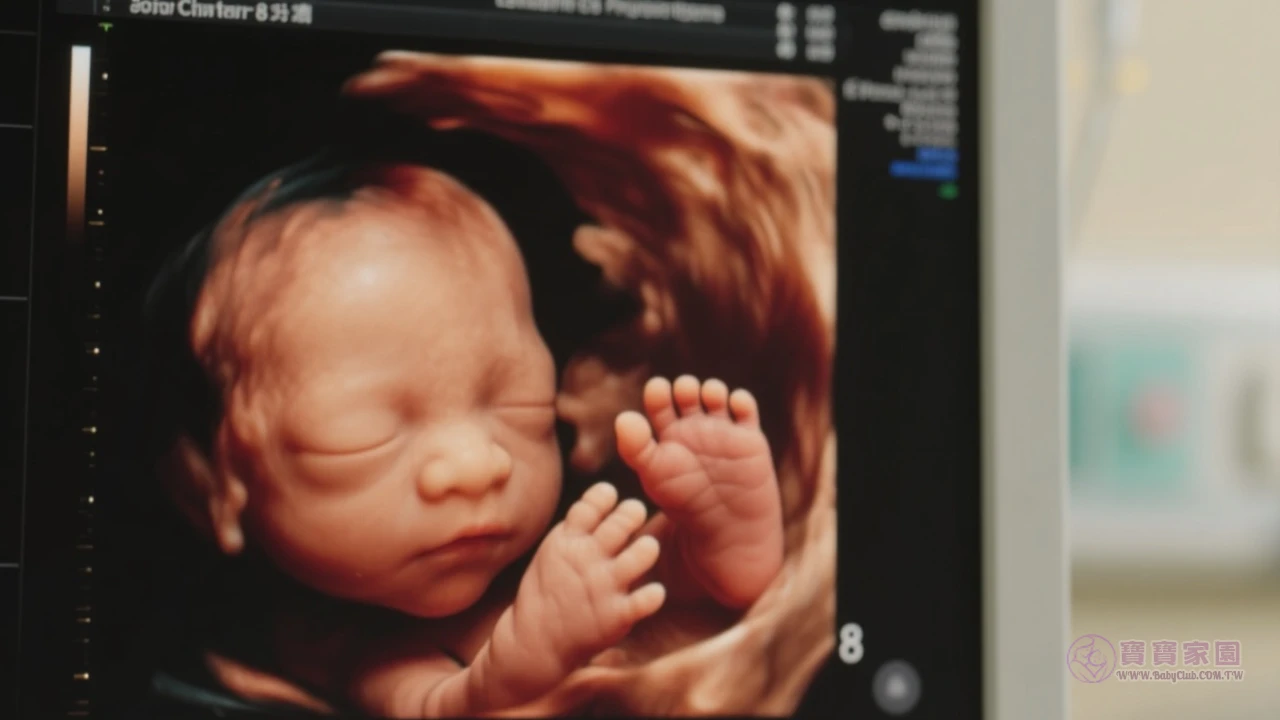

懷孕第8週必看 | 胎兒手指成形、孕吐應對全攻略|孕前期1-3月指南2懷孕進入第8週,雖然肚子還看不出明顯變化,但妳可能已經感受到褲子變緊、胸部脹痛等身體變化。 這個階段有些準媽媽會食慾大增,更多人則是對食物氣味特別敏感甚至反胃,讓我們一起來看看懷孕第8週的重要發展和注意事項吧! 懷孕第8週快速重點 本週胎兒成長里程碑 寶寶正以驚人速度成長!此時胚胎已開始形成嘴唇、鼻子、眼瞼等五官,生殖器官也進入發展階段。 雖然手腳還像蹼狀組...標籤:懷孕第2個月

懷孕12週完整指南 | 寶寶如檸檬大,孕媽必知症狀與產檢重點3懷孕12週代表妳即將告別孕初期,進入相對穩定的孕中期!這時候的寶寶已經長到檸檬大小囉~ 本文整理媽咪們最關心的胎兒發展狀態、常見產檢項目,以及舒緩不適的小秘訣,讓妳安心迎接孕期新階段♪ 孕期12週快速重點 寶寶本週發展里程碑 此時胎兒開始練習吞嚥動作,手指腳趾也完全分開啦!透過超音波可能會看到寶寶在羊水中揮舞小手,雖然媽咪還感覺不到胎動,但內部器官正如火如荼...標籤:懷孕第3個月